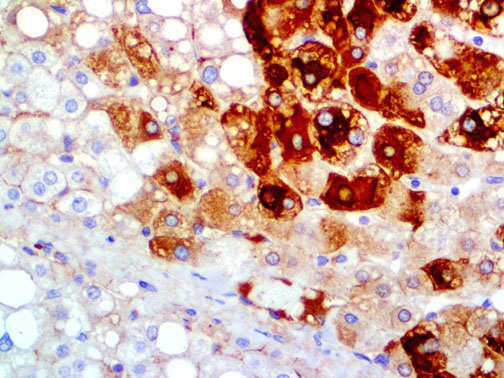

It is the ICU physician who is most likely to witness one of the deadliest manifestations of the abnormal immunological response, the cytokine storm syndrome (CSS). This response is also referred to by some as the cytokine release syndrome (CRS). CSS is characterized by continuous activation and expansion of macrophage and lymphocyte populations, which secrete large amounts of cytokines, causing the cytokine storm. This massive cytokine release is akin to hemophagocytic lymphohistiocytosis (HLH) disease, a syndrome characterized by initial unchecked and persistent activation of cytotoxic T lymphocytes and NK cells.

Clinical and laboratory manifestations of HLH include fever, enlarged liver and/or spleen, neurologic dysfunction, coagulopathy, liver dysfunction, cytopenias (i.e., low levels of erythrocytes, leukocytes, and/or platelets), hypertriglyceridemia, hyperferritinemia, hemophagocytosis, and eventually diminished NK cell activity as the immune system becomes progressively paralyzed. HLH can be familial (primary HLH) or secondary to another disease process (sHLH), such as rheumatic disease, in which it is referred to as macrophage activation syndrome (MAS, characterized by elevated ferritin).

This activation induces inflammatory monocytes to highly express IL-6, starting a localized and then systemic cascade effect that results in hyperproduction of IL-6, which accelerates the inflammatory process. Because IL-6 also increases vascular permeability, excessive levels cause blood vessels to become very leaky. This, along with clotting factors released from vascular endothelial cells, stimulates the coagulation cascade, resulting in microthrombosis (tiny clots), which leads to ischemia and tissue death of the kidney, intestines, heart, liver, brain and extremities.